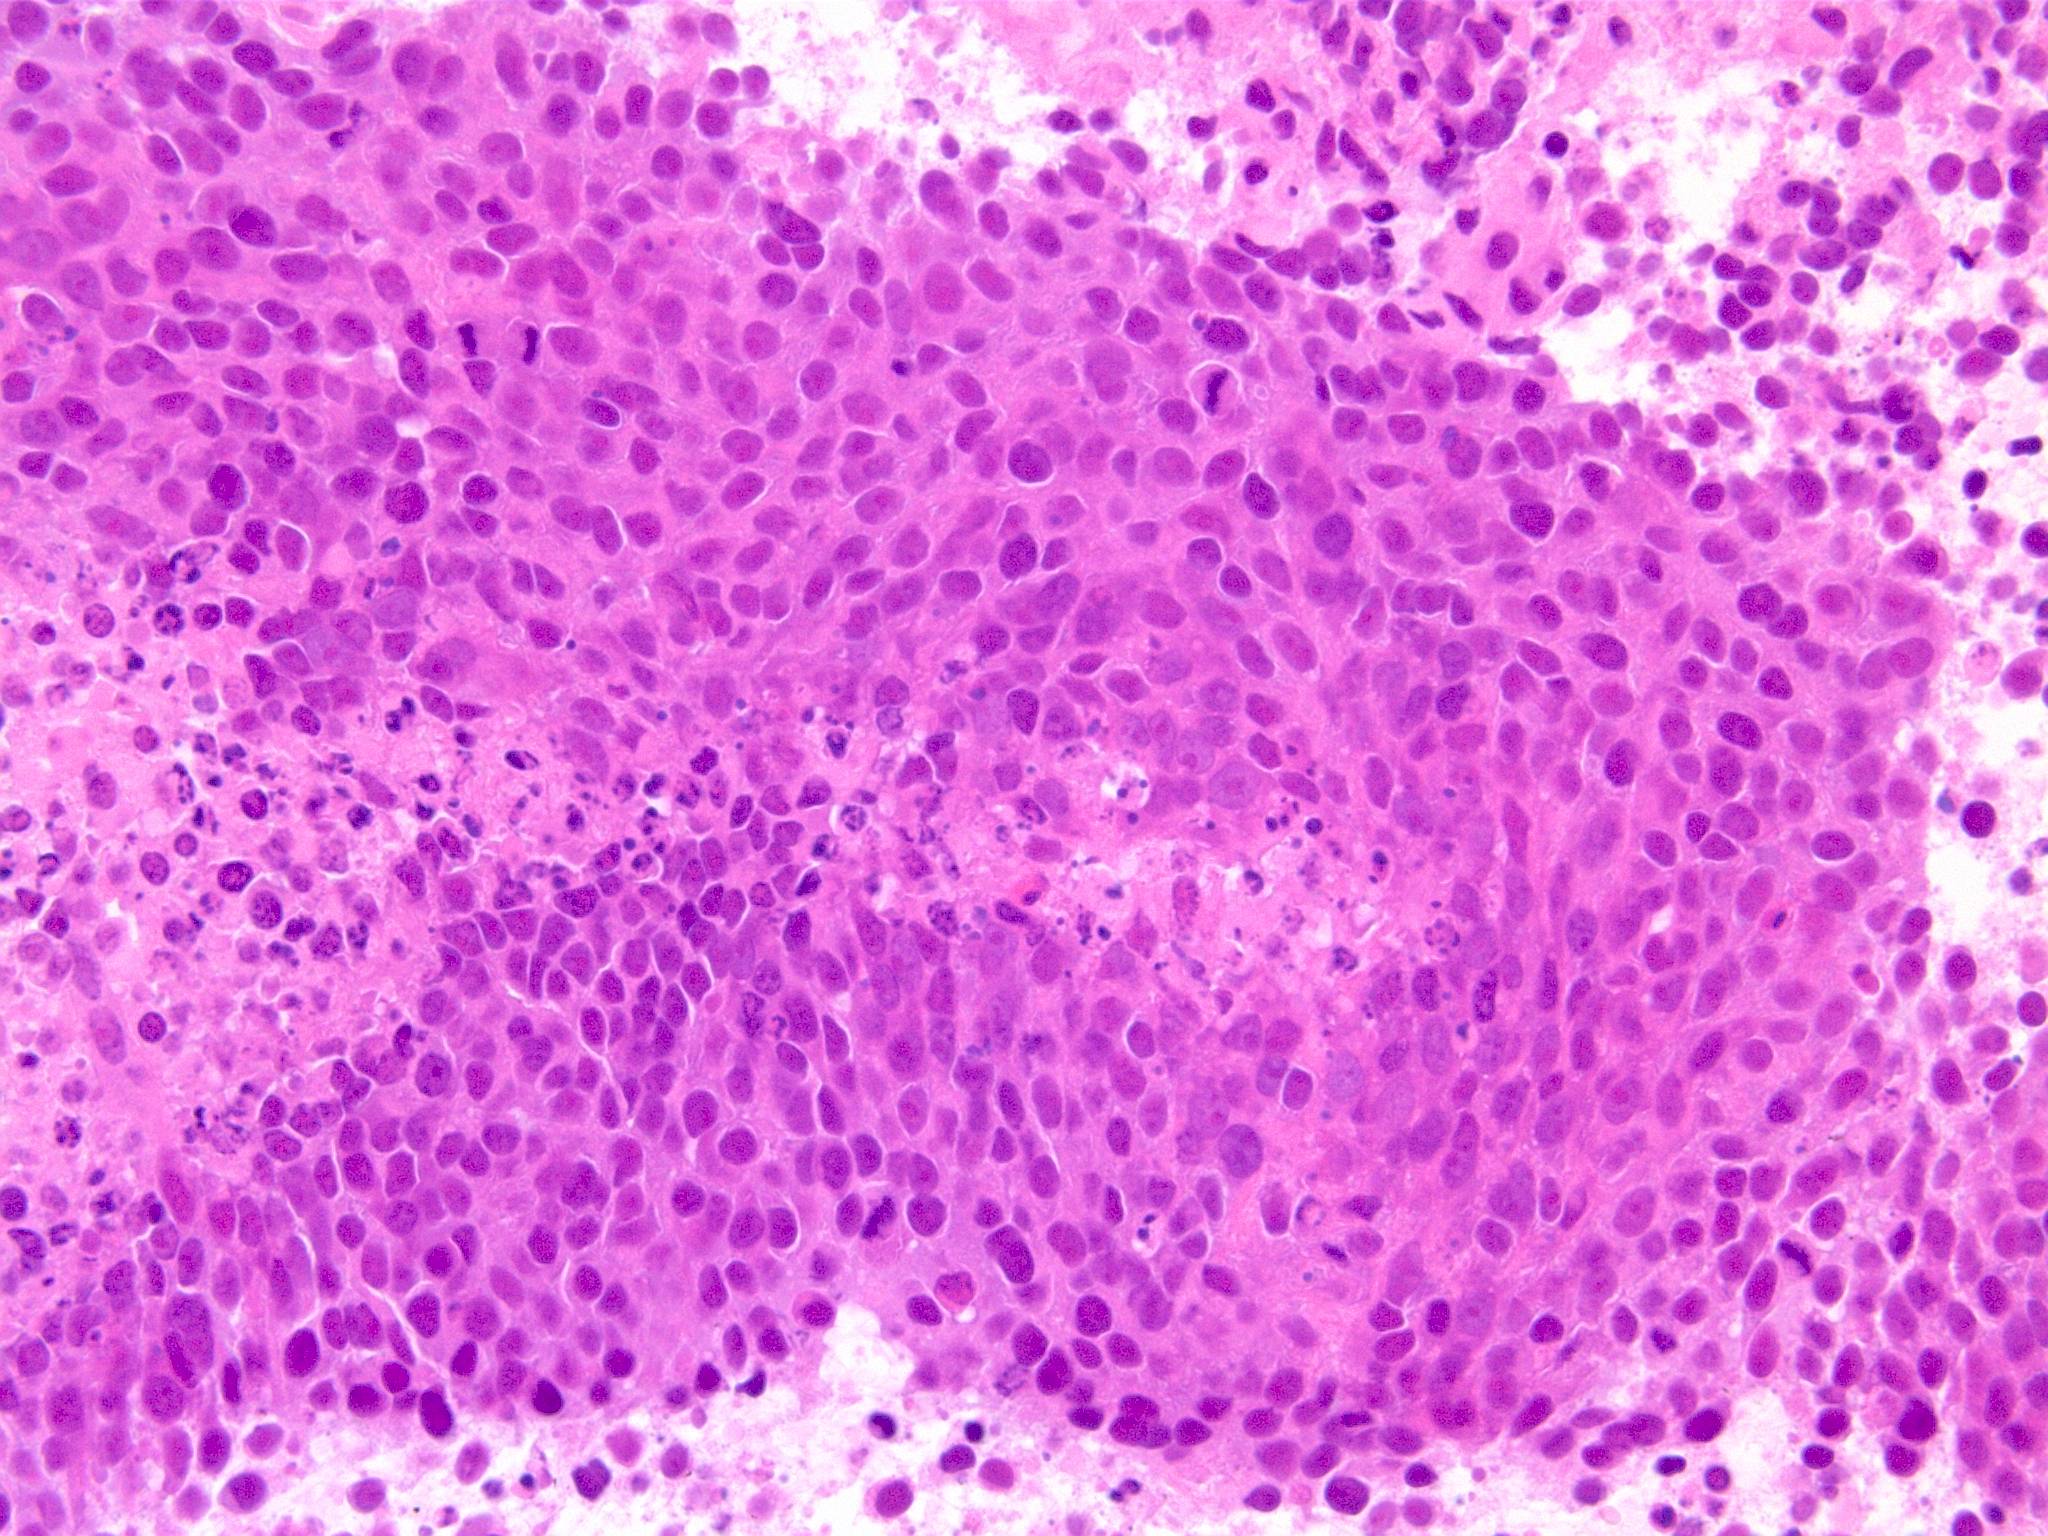

副鼻腔腫瘤生検組織

日本病理学会中部支部交見会のスライドより。(S.Suzuki Dr.)